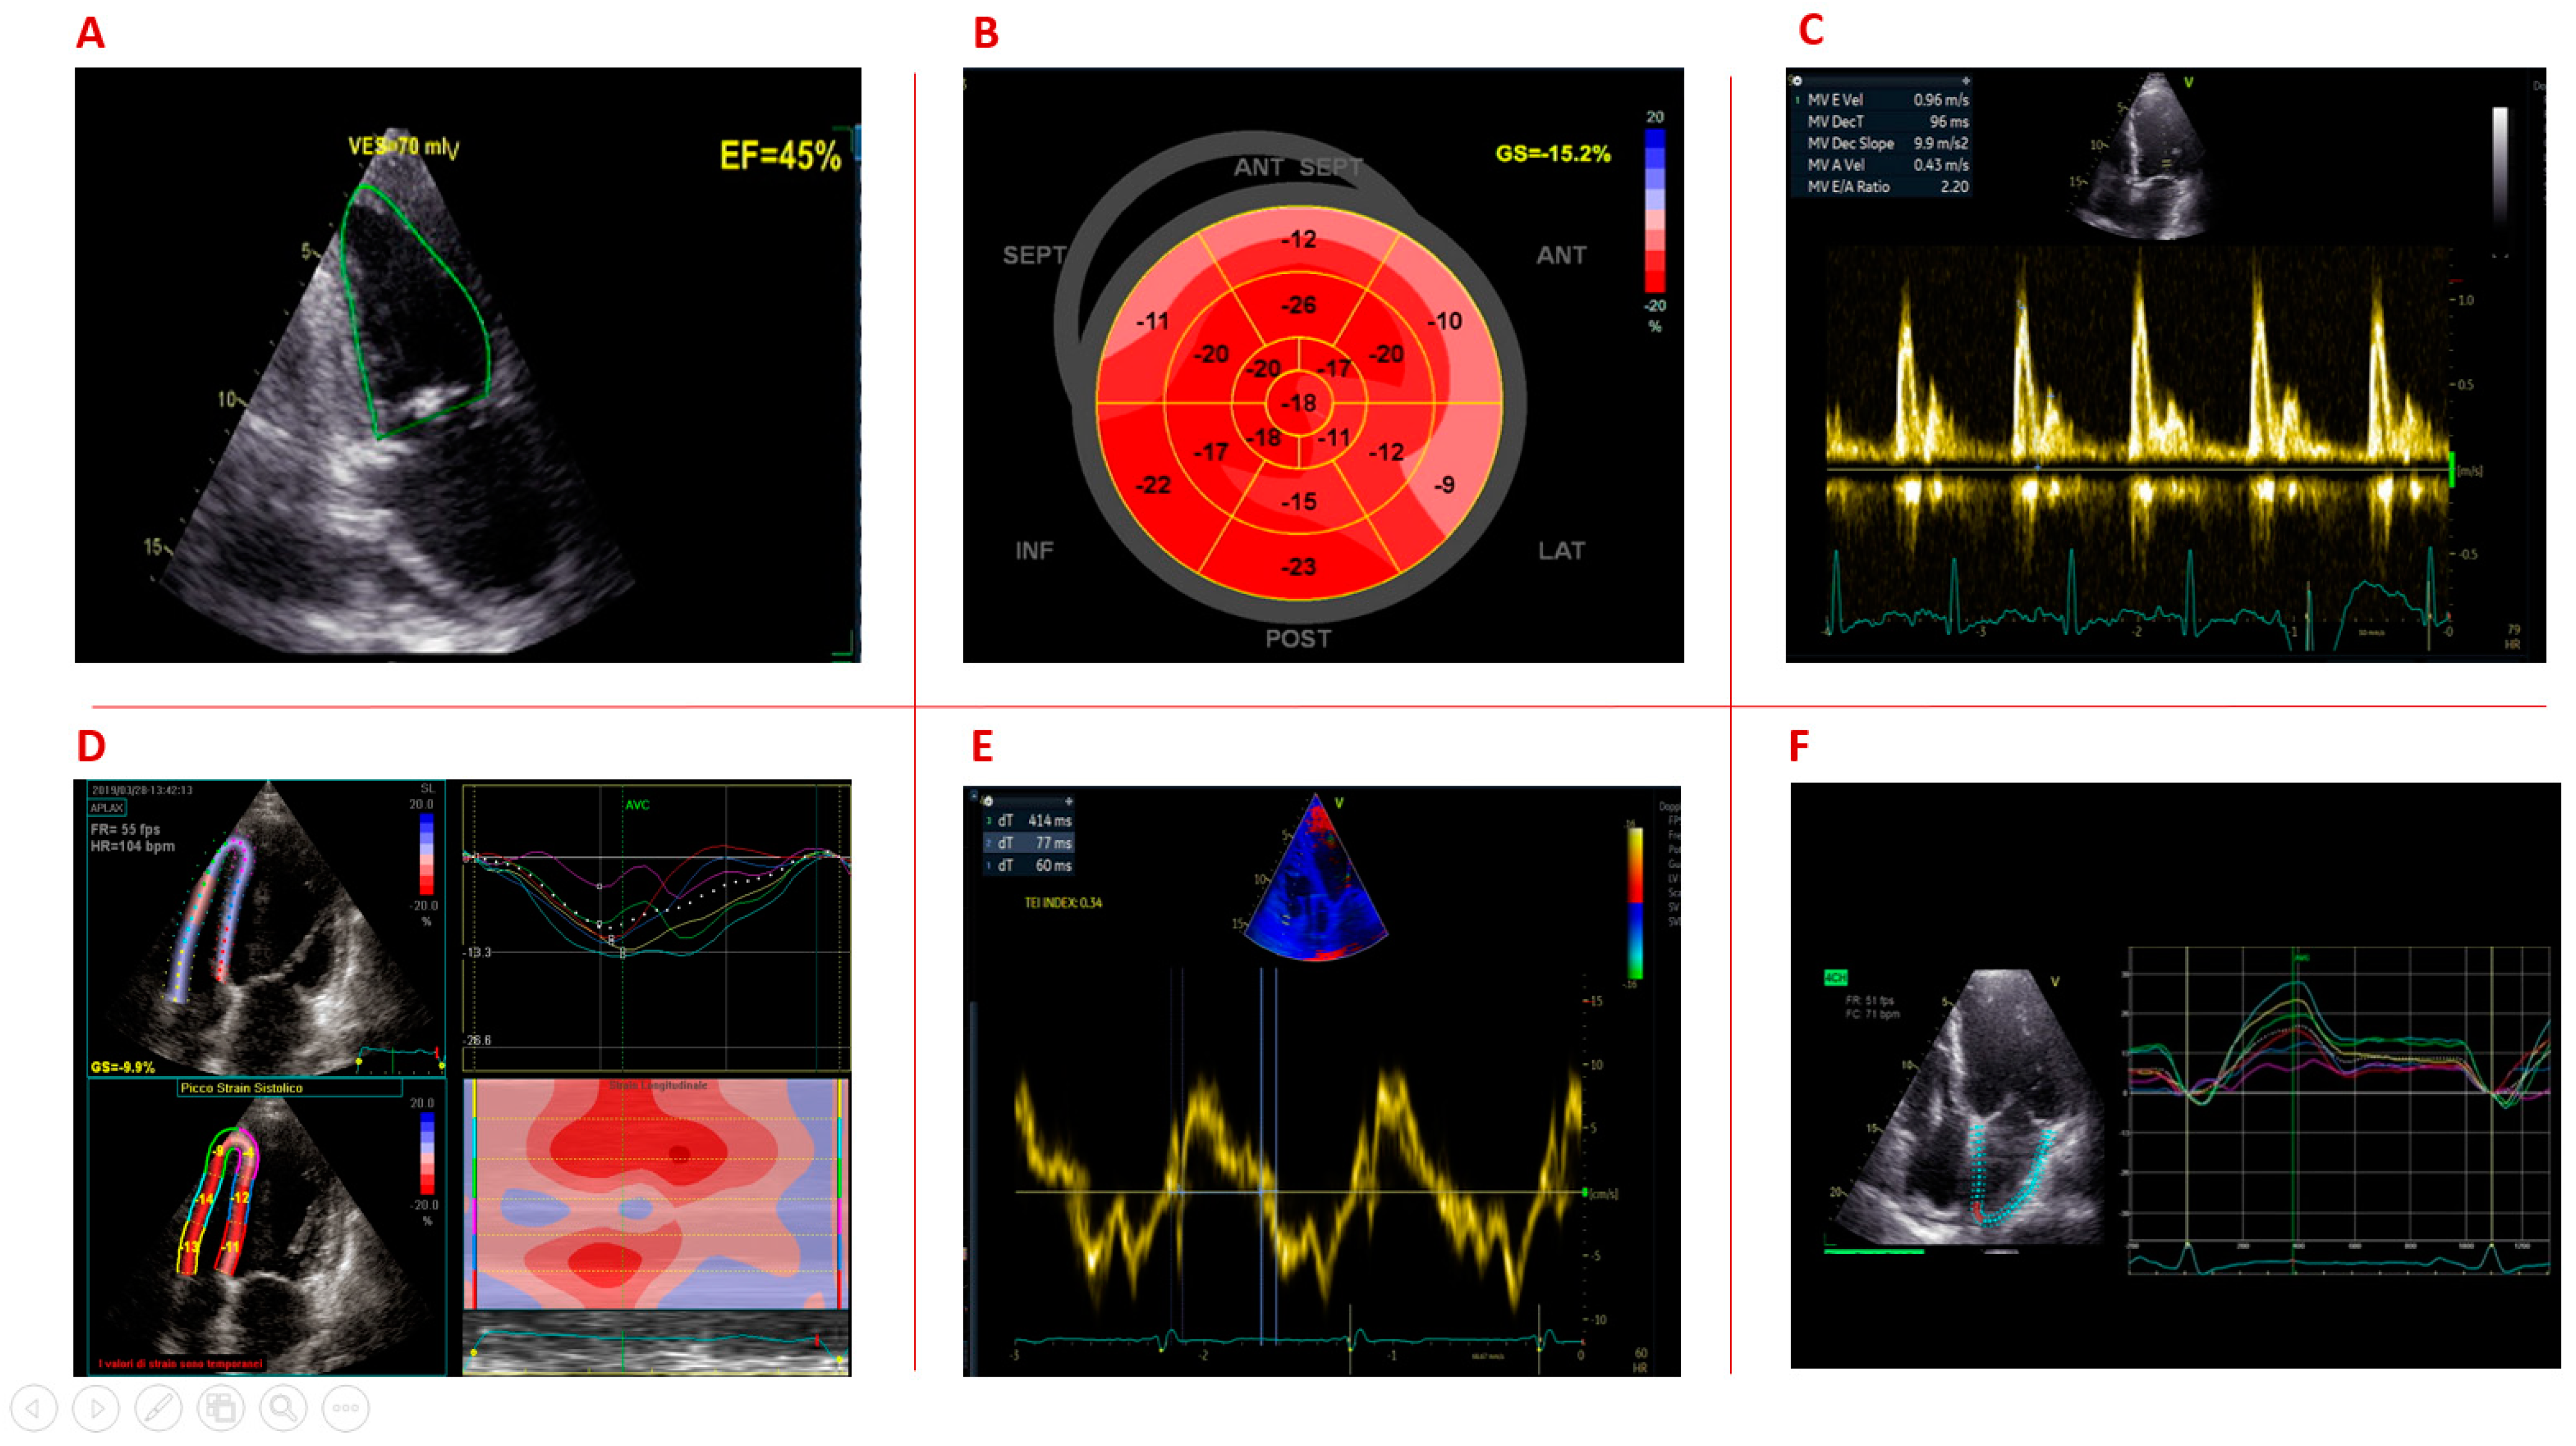

1.1. Left Ventricular Systolic Dysfunction

1.2. Left Ventricular Strain

1.3. Left Ventricular Diastolic Dysfunction

1.4. Right Ventricular Function

1.5. Left Atrial Function

| Garcia [29] | 2017 | Prospective study | 33 | 38.2 ± 12.9 | 33 | LV GLS | DM1 patients exhibited significantly altered LV GLS, particularly at the apex (−20.0 ± 3.3 vs. −22.7 ± 3.1; p < 0.001), as compared with controls. |

| Garcia [13] | 2017 | Prospective study | 46 | 40 [29–49] | - | LV GLS | LV GLS (cut-off value of −17.2%) predict cardiovascular events, regardless LVEF. |

| Petri [28] | 2014 | Cross-sectional study | 129 | 44 (15) | - | GLS | The prevalence of abnormal GLS was 21.7% Abnormal GLS was above −15.9%; 60% had preserved LVEF> 50%. |

| Sousa [27] | 2013 | Case–control study | 25 | 36.7 ± 12.5 | 13 | GLS | DM1 patients showed a lower GLS than controls (−16.6 ± 3.6% vs. −18.7 ± 1.8%, p = 0.022). GLS correlates with PR interval duration. |

| Lindqvist [46] | 2010 | Case–control study | 36 | 45 ± 10 | 16 | Right ventricular function by Doppler and RV strain | DM1 patients showed a prolonged IVCT and IRVT (both p < 0.05); shorter ET (p < 0.05); a higher right ventricular–right atrial pressure drop (23 ± 7 vs. 18 ± 2 mm Hg, p < 0.05); a reduction in RV free wall Sm (p < 0.001) and Am velocities (p < 0.05); a reduction in RV free wall systolic strain (−21.1 ± 8.6 vs. −31.2 ± 11%, p < 0.001). |

| Ozyigit [34] | 2010 | Case–control study | 21 | 32.3 ± 12.3 | 21 | Right ventricular function by Doppler | DM1 patients showed a reduction in peak velocity (cm/s) of Sm (12.38 ± 2.91 versus 14.40 ± 2.25 p = 0.016), Em (11.91 ± 3.54 versus 14.39 ± 3.87 p = 0.037); Tei index was significantly higher in DM1 patients compared with controls (0.27 ± 0.17, p = 0.013). |

| Fayssoil [16] | 2014 | Case–control study | 26 | 45.1 (10.9) | 13 | Diastolic function | Increased left atrium diameter and increased mitral deceleration time compared with healthy controls; no differences were found regarding mean peak E/A mitral ratio, mean peak lateral early diastolic velocity and mean peak septal early diastolic velocity. |

| Wahbi [26] | 2011 | Case–control study | 39 | 37.5 ± 12.1 | 39 | LV GLS | Speckle tracking GLS was able to identify LV contractility abnormalities in DM1 patients with normal LVEF. DM1 patients showed a lower apical 4 chambers GLS compared to controls (−17.8 ± 2.5 vs. −19.2 ± 2.3 p = 0.01), which significantly correlated with PR interval. |